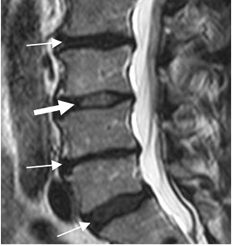

Fig 21. Articulaciones intervertebrales lumbares.

A: Rx oblicua, B: TAC reconstrucción sagital y C: TAC axial. Articulaciones intervertebrales normales. La faceta anterior corresponde a la vértebra inferior (Flecha delgada) y la posterior a la superior. (Flecha gruesa).

Fig 22. Articulaciones intervertebrales normales.

A: RM axial en T1 y B: RM axial en T2. Articulaciones intervertebrales normales con espacio ocupado por grasa, hiperintensa en ambas secuencias.